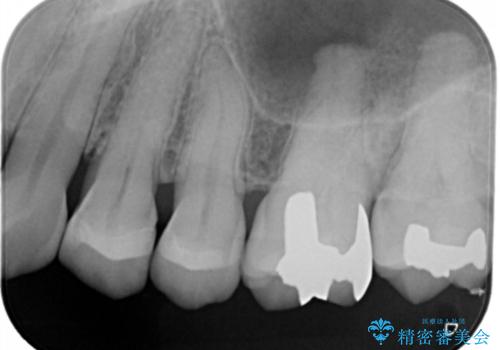

- 左上奥歯の銀歯のやり変えを希望された患者様です。

白くしたいとの事だったので形態・切削量を考慮し、セラミックインレーでの治療を計画しました。

保険材料と比較し、セラミックは劣化しない材料なので二次的な虫歯を防ぐことが出来ます。